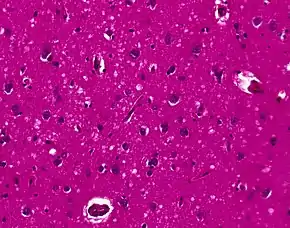

Spongiform change in CJD

Testing of tissue remains the most definitive way of confirming the diagnosis of CJD, although it must be recognized that even biopsy is not always conclusive.[51]

The classic histologic appearance is spongiform change in the gray matter: the presence of many round vacuoles from one to 50 micrometers in the neuropil, in all six cortical layers in the cerebral cortex or with diffuse involvement of the cerebellar molecular layer.[54] These vacuoles appear glassy or eosinophilic and may coalesce. Neuronal loss and gliosis are also seen.[55] Plaques of amyloid-like material can be seen in the neocortex in some cases of CJD.[56]

However, extra-neuronal vacuolization can also be seen in other disease states. Diffuse cortical vacuolization occurs in Alzheimer's disease, and superficial cortical vacuolization occurs in ischemia and frontotemporal dementia. These vacuoles appear clear and punched-out. Larger vacuoles encircling neurons, vessels, and glia are a possible processing artifact.[53]